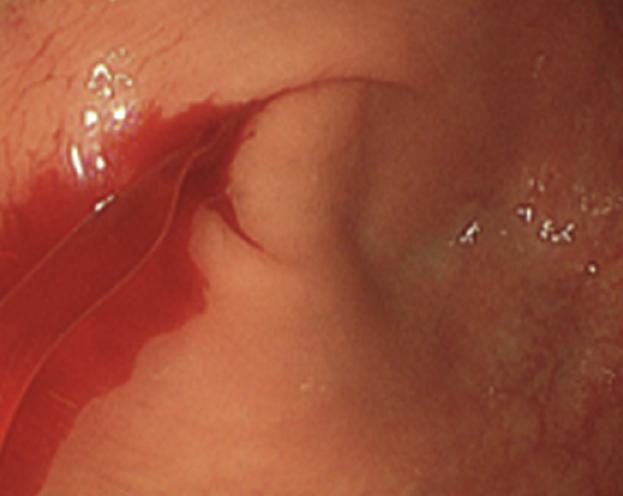

肠道出血严重竟是小虫在作祟

通过胃肠镜检查,竟发现小清肠道内布满多条寄生虫。连接诊医生都感到惊讶,有的寄生虫甚至已经将胃粘膜咬住,导致肠道损伤出血。